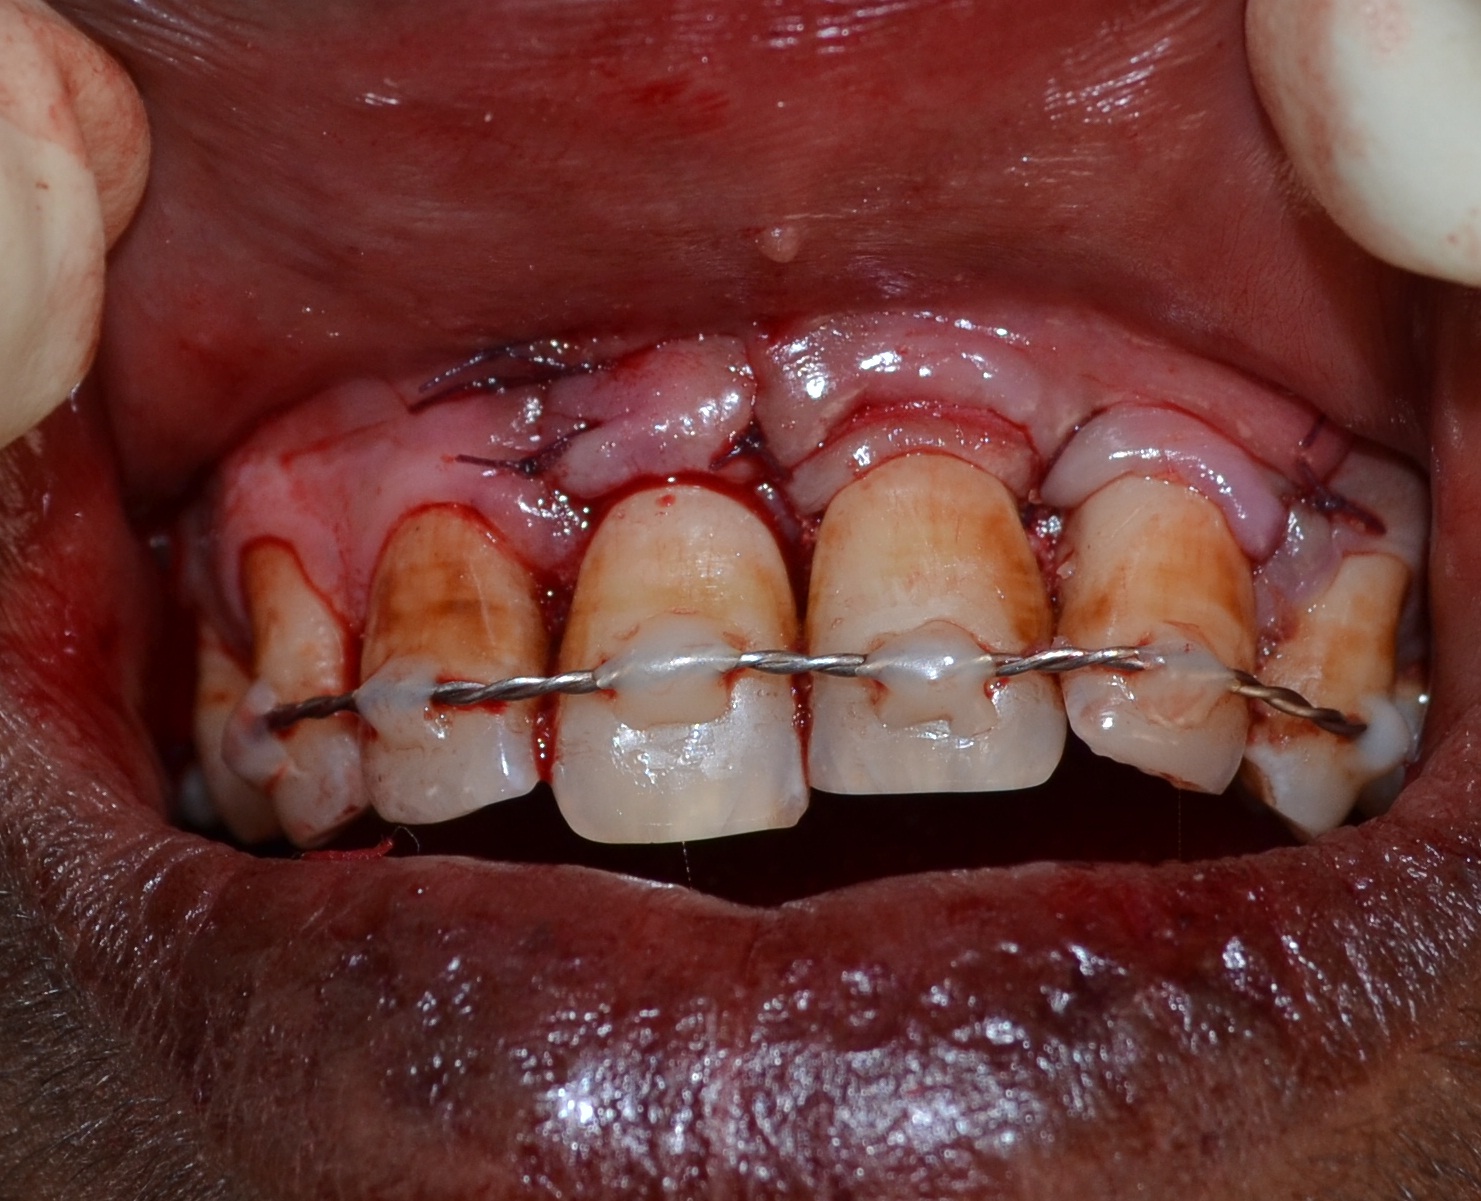

Surgical Re-entry: Tooth was re-splinted and full thickness mucoperiosteal flap was raised revealing bone formation in the apical 1/3rd of the root [Table/Fig-9]. The middle and coronal third of the root were still deficient in bone support. Hence, the defect wall was decorticated [1] using round bur, followed by placement of Xenograft (Osseomold, Encoll, USA). Coronally advanced flap with Sub-epithelial Connective Tissue Graft (SCGT), along with PRF was used for recession coverage [Table/Fig-10]. Vicryl (5-0) sutures (Ethicon, USA) were used to stabilize the graft and the flap [Table/Fig-11]. Periodontal dressing (Coe-Pack) was placed. On 10th post-operative day sutures were removed.

Recession coverage using SCTG and PRF.

Suturing post-recession coverage using SCTG and PRF.